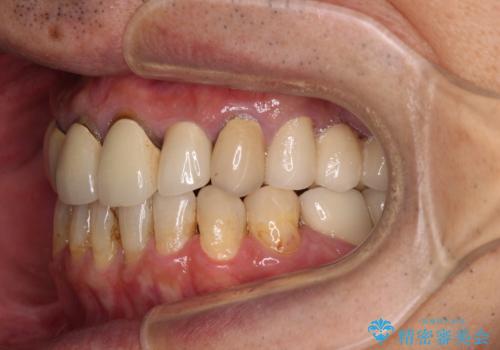

- 抜歯した歯や抜歯が必要と思われる歯を放置したため、奥歯に不快を感じているとのことで来院された患者様です。

右下は奥歯が抜歯したスペースを塞いでしまい、左下はブリッジの支台歯の1つが破折している状態でした。

また、下顎前歯にはスペースがあり、コンポジットレジンでスペースを閉じている状態だったので、前歯のスペースを解消しつつ、奥歯にスペースを獲得するよう矯正治療を行うこととしました。

並行して左下にはインプラントを埋入し、上顎臼歯部の気になる部分も根管治療などを進めて行き、矯正治療を終えると同時に補綴治療を行うこととしました。

奥歯1歯分を動かすには時間がかかるため、矯正治療には思いの外時間がかかりました。

痛みのある奥歯は必要に応じて根管治療を行い、左下インプラントは角化歯肉の移植により清掃性を向上させ、気になっていた部分をしっかりと改善させることができました。